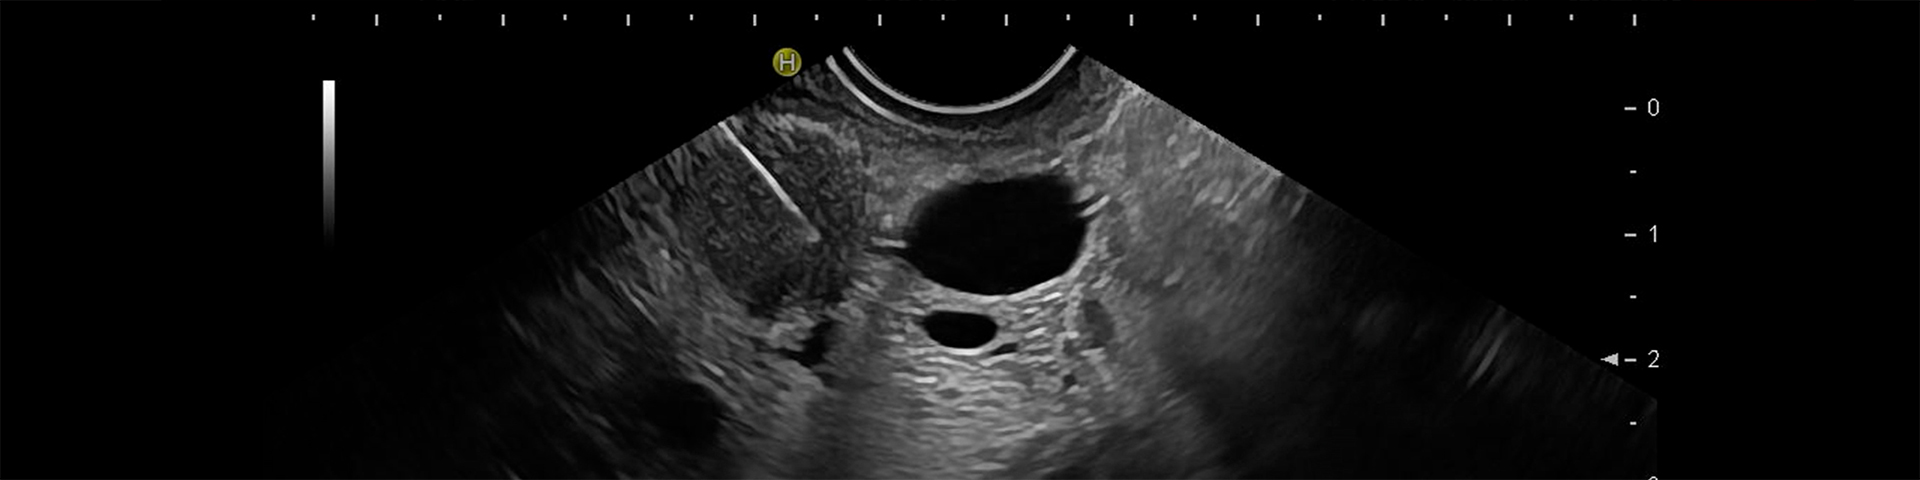

Als endoskopischen Ultraschall (EUS) bezeichnet man die Kombination aus Endoskopie und Sonographie. Mittels Feinnadelpunktion ist eine Gewebegewinnung aus Strukturen möglich, die mit anderen Biopsiemethoden nicht oder nur mit großer Invasivität und damit einhergehend höherem Risiko zugänglich sind.

Primäres Einsatzgebiet ist die zytopathologische Diagnose von Gewebewucherungen im Verdauungssystem sowie den umliegenden Lymphknoten.